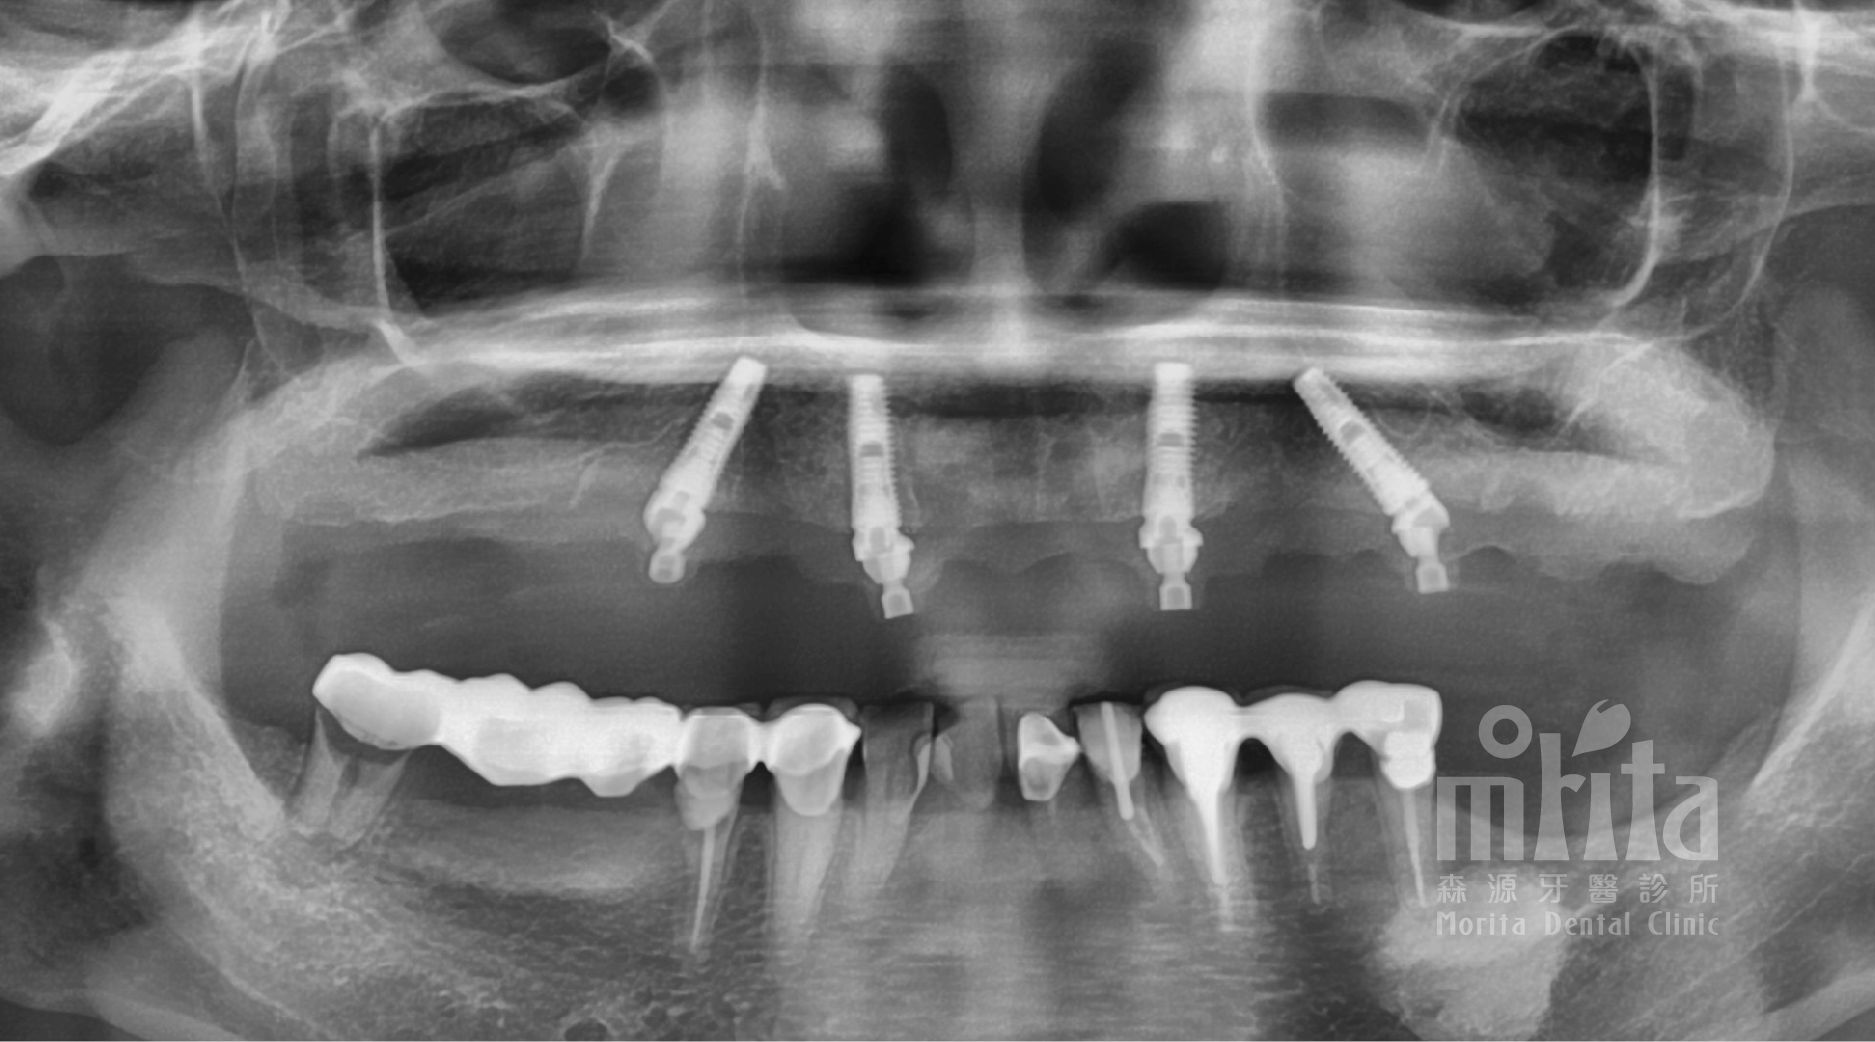

一日假牙除了需要集結手術醫師,假牙醫師,麻醉醫師配合之外,也需要專業的一日假牙資深技師一同合作,在治療中的特定階段馬上在在診所同步進行假牙的製作。

一日假牙取模時,會使用傳統印模與數位印模的融合的特殊技法,反覆驗證模型準確度,再進行正式假牙的製作。

經由多次在模型上,以及呂阿姨的口內驗證與調整後,最後完成正式假牙的製作。